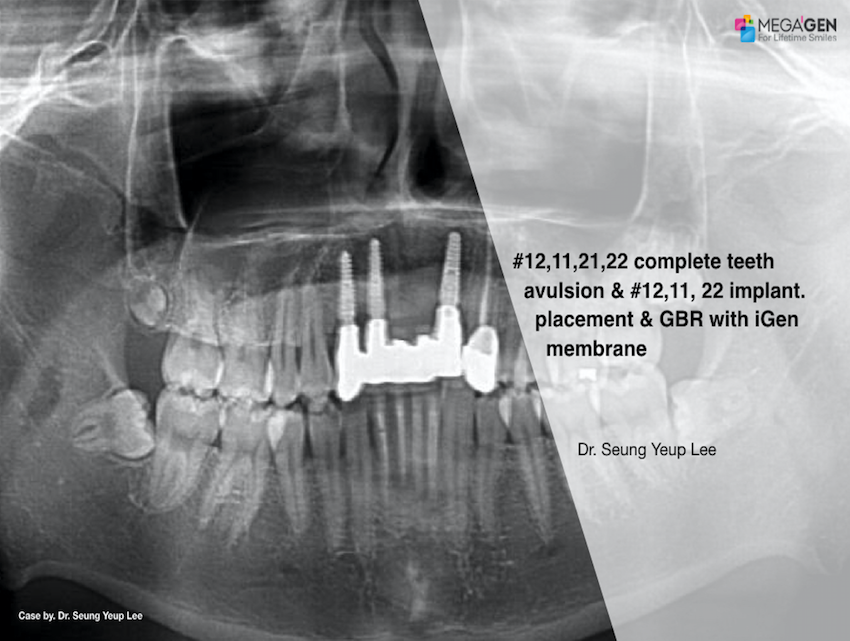

e.g. product name, treatment solution, author, clinician name